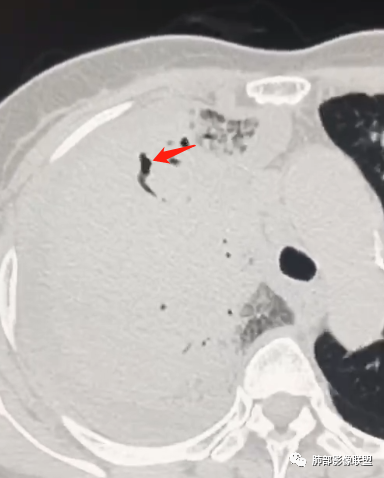

还有一次CT:

这也是我判断失误的原因之一:树芽征

重建后就是血管束增粗

我以为树芽征,其实是中轴间质增厚

没看清楚,只看到表面,考虑小气道结节,那些是支气管扩张+空洞,所以考虑结核,其实两点都错了,谢谢赖老师。

应该要二元.看这样的支气管。